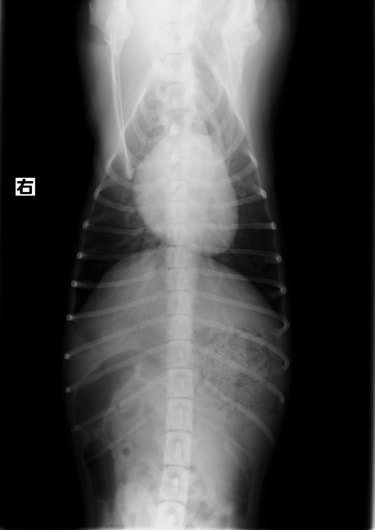

症例6:【ACVIM StageD ビーグル 10歳 去勢雄】

A:胸部レントゲン写真 側面像

B:胸部レントゲン写真 正面像

左側胸壁心尖部領域を最強点とするLevine 5/6の収縮期性心雑音が聴取された。安静時にも咳が認められる。胸部レントゲン検査において重度の心拡大が及び肺水腫が認められた。超音波検査では、重度の僧帽弁閉鎖不全、三尖弁閉鎖不全が認められた。三尖弁逆流速度から肺高血圧症が示唆された。ACE阻害薬、ピモベンダン、硝酸イソソルビド徐放剤、ベラプロストナトリウム、利尿剤としてフロセミド及びスピロノラクトンを用いて治療を行っている。